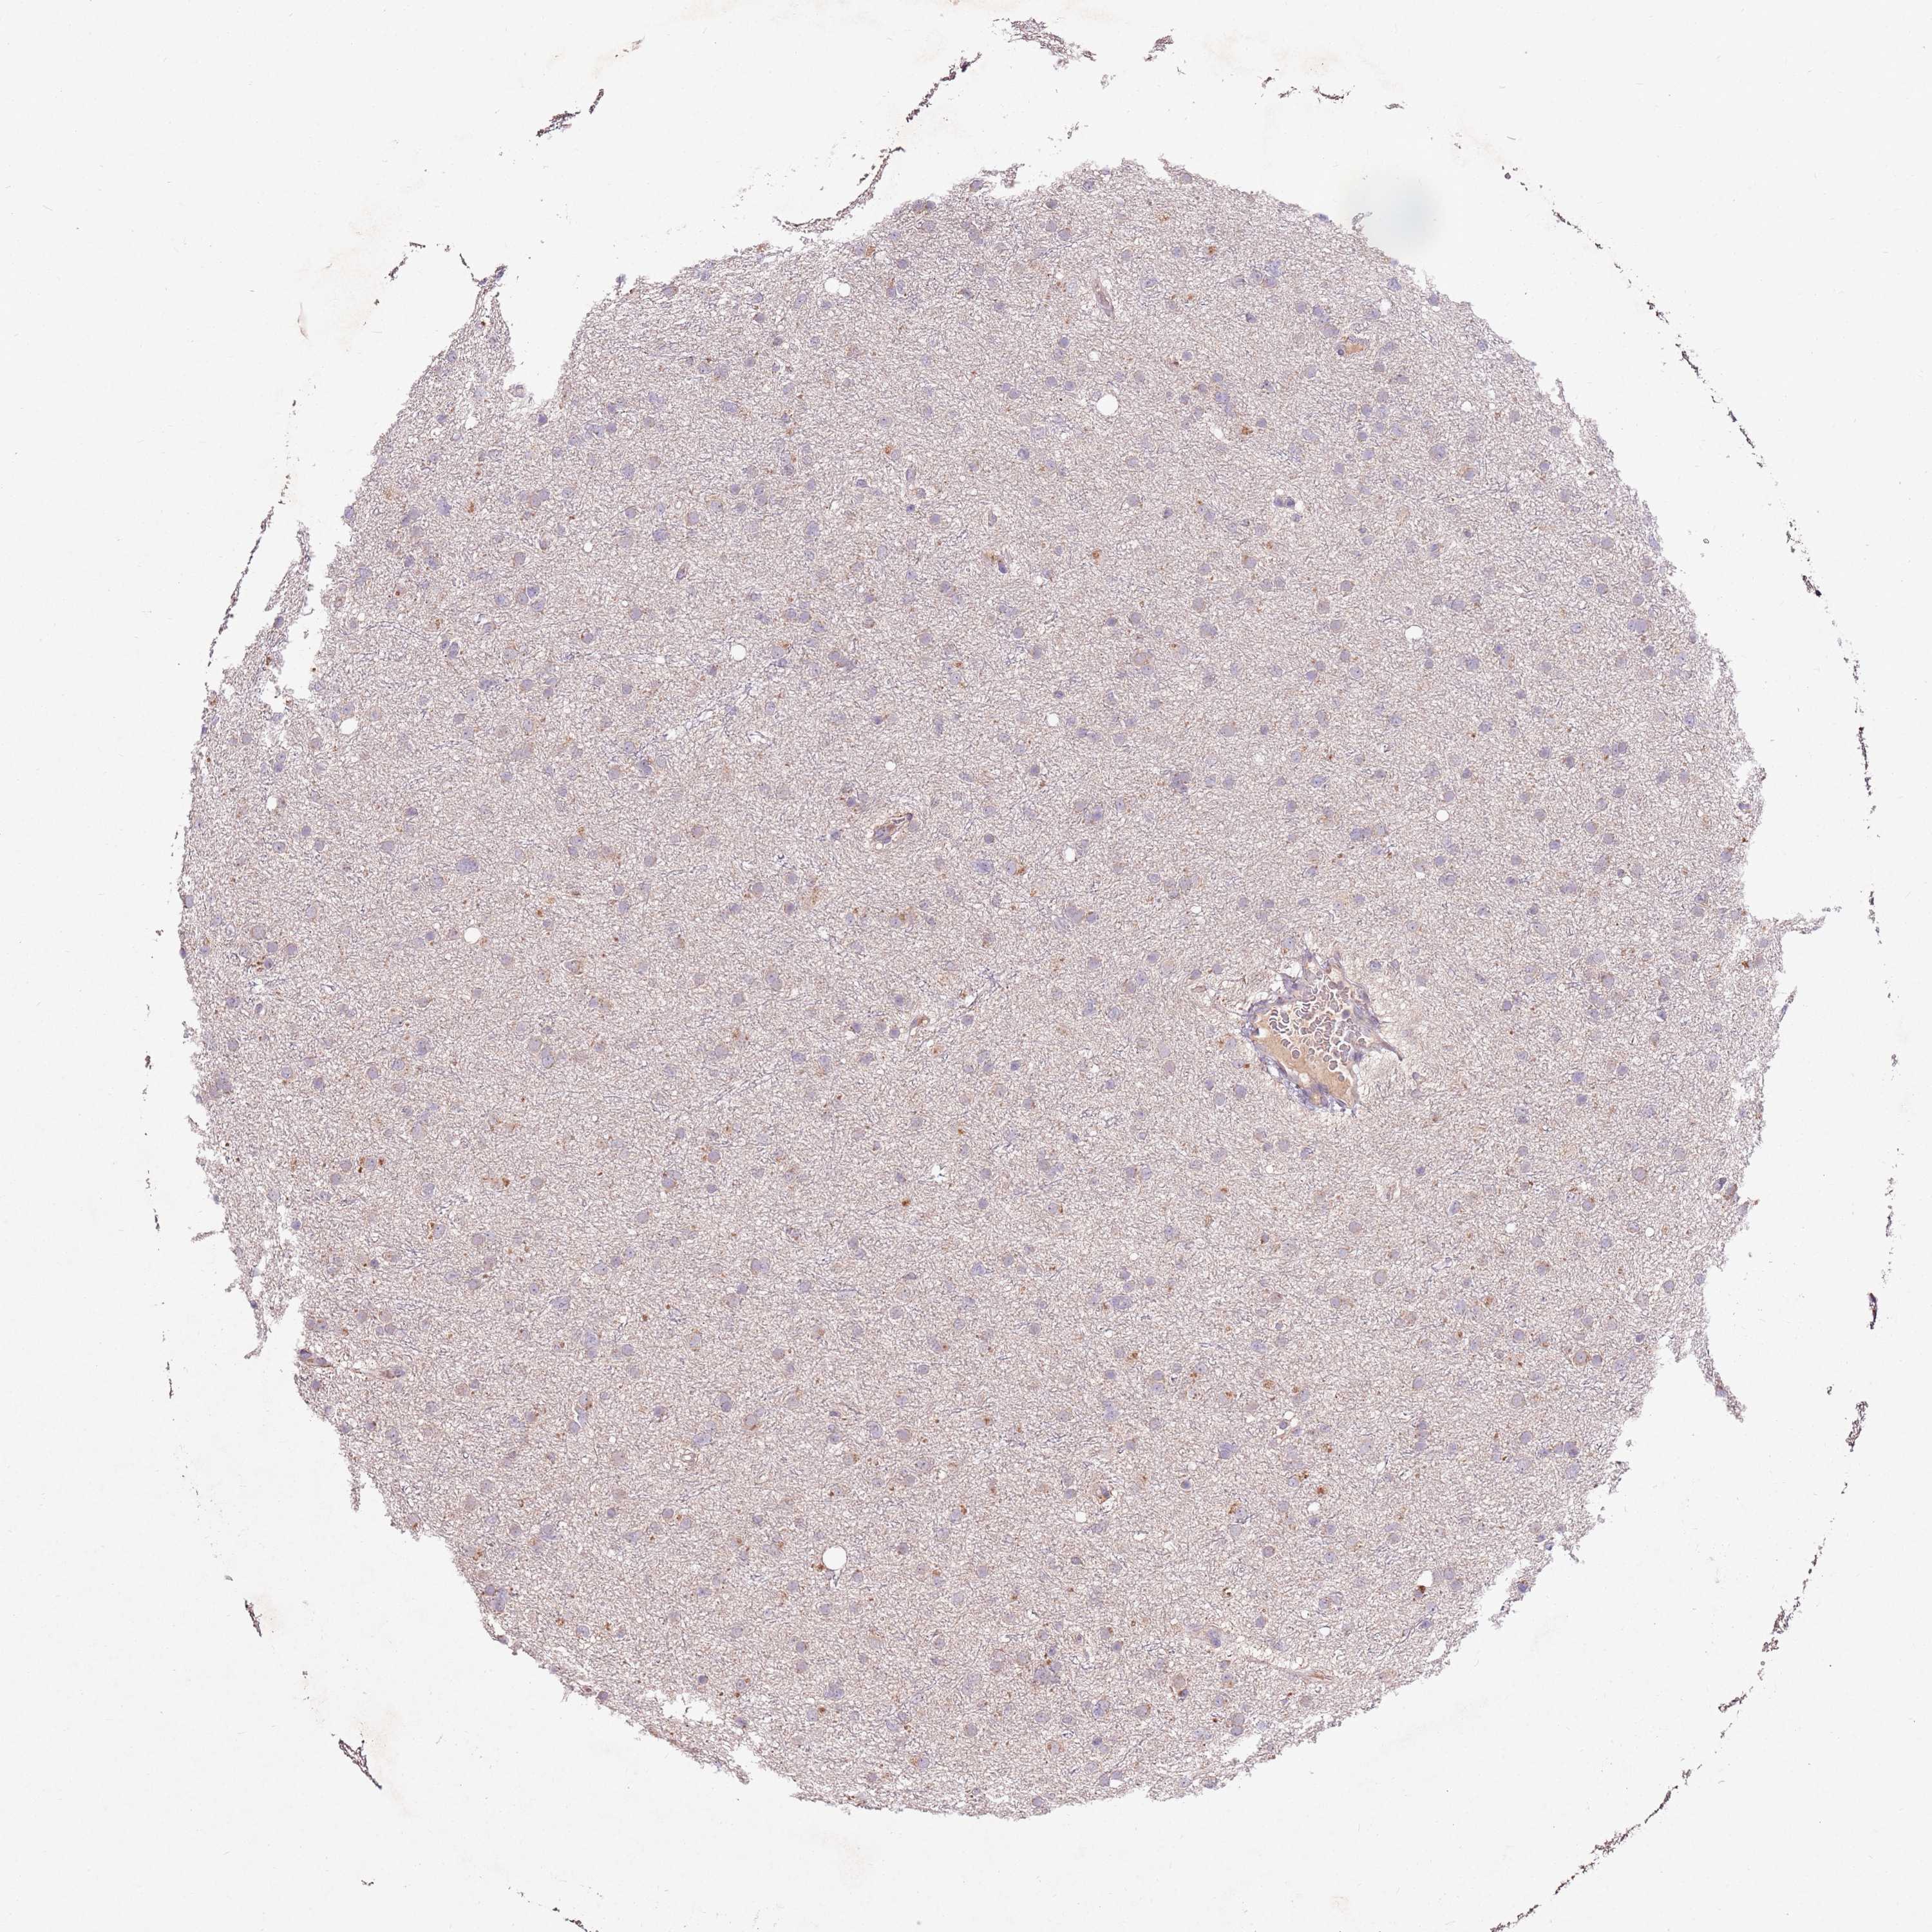

GLIOMA - Protein expressioni

A mouse-over function shows sample information and annotation data. Click on an image to view it in a full screen mode. Samples can be filtered based on level of antibody staining by selecting one or several of the following categories: high, medium, low and not detected. The assay and annotation is described here.

Note that samples used for immunohistochemistry by the Human Protein Atlas do not correspond to samples in the TCGA dataset.

Antibody stainingi

Antibody staining in the annotated cell types in the current human tissue is reported as not detected, low, medium, or high, based on conventional immunohistochemistry profiling in selected tissues. This score is based on the combination of the staining intensity and fraction of stained cells.

Each image is clickable and will lead to virtual microscopy that enables deeper exploration of all samples and also displays staining intensity scores, fraction scores and subcellular localization as well as patient and tissue information for each sample.

Antibody HPA047050

Antibody HPA050583

Staining

High

Medium

Low

Not detected

Intensity

Strong

Moderate

Weak

Negative

Quantity

>75%

75%-25%

<25%

None

Location

Nuclear

Cytoplasmic/membranous

Cytoplasmic/membranous,nuclear

Glioma, malignant, High grade

Glioma, malignant, Low grade

Glioblastoma, NOS